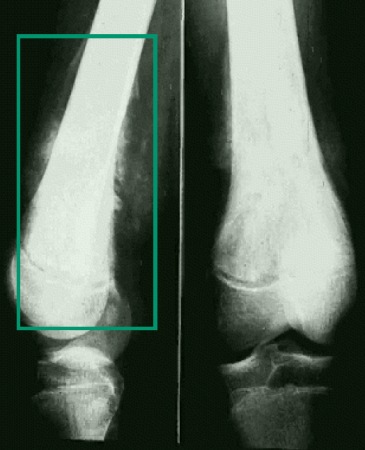

Malignant disease (leukaemia, lymphoma, primary bone tumour) [Figure caption and citation for the preceding image starts]: Malignant bone tumour (x-ray)From Dr Foster's personal collection; used with permission [Citation ends].